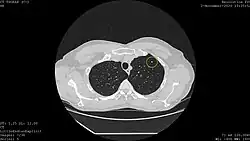

![]() Computed tomography (CT) scanner, a commonly recommended screening technique | |

Results from large randomized studies have recently prompted a large number of professional organizations and governmental agencies in the U.S. to now recommend lung cancer screening in select populations. The 3 main types of lung cancer screening are low-dose, computerized tomographic (LDCT) screening, chest x-rays, and sputum cytology tests.[4] Currently multiple professional organizations, as well as the United States Preventive Services Task Force (USPSTF), the Centers for Medicare and Medicaid Services (CMS) and the European Commission's science advisors[5] concur and endorse low-dose, computerized tomographic screening for individuals at high-risk of lung cancer.